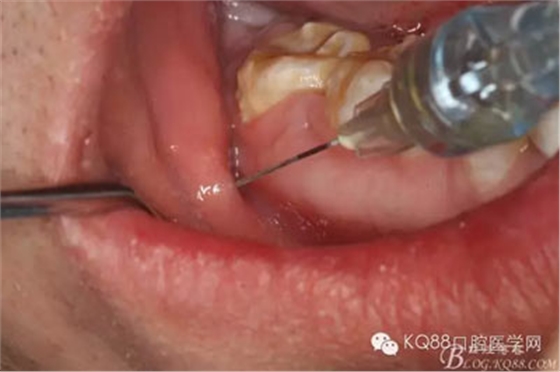

圖5.局部無(wú)痛阻滯麻醉+頰側(cè)粘膜浸潤(rùn)麻醉